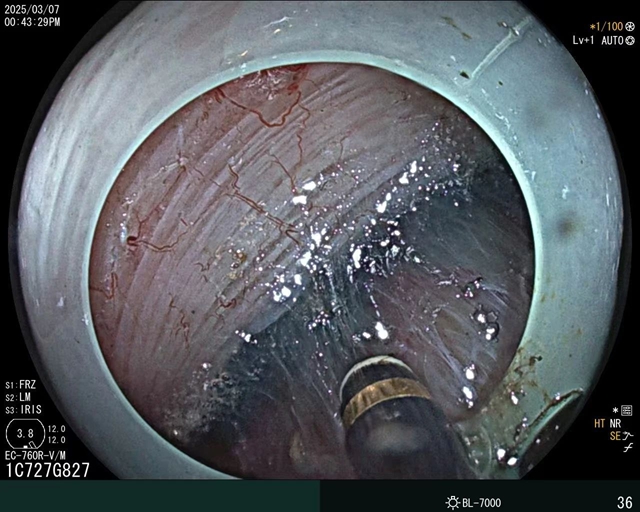

作为科室肠镜的“扛把子”,3万多例肠镜检查让他练出了“0.1毫米级”的操作精度,1000多例早期肠癌治疗让他成了肠道里的“拆弹专家”。

只见余腾江拿着肠镜,开始“肠道穿花线”,从肛门进镜到阑尾,不开刀,用内镜器械把阑尾腺瘤当“核桃”完整取出,保留阑尾。

“很多人怕肠镜,其实我的肠镜检查就像给肠道做‘全景VR扫描'。”余腾江指着肠镜演示:这镜头比手机前置摄像头还高清,边扫边给肠道修图,遇到息肉直接用圈套器一键清除。”

半年前,26岁的小李无明显诱因出现腹部隐痛,伴大便次数增多,平均每天要拉肚子2-3次。肠镜检查提示:结肠息肉、结直肠炎(轻度),决定实施内镜下黏膜切除术(直肠息肉EMR术)。

术中,谭茂华在内窥镜下往黏膜下注射生理盐水,使肿物隆起、剥离、最后切除。